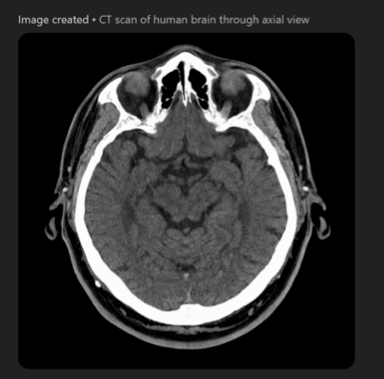

Coming back to the generative AI we mentioned at the start of the article, during our interview Denker and Barbano decided to conduct an experiment. They asked ChatGPT to produce a CT image. The result, shown below, claims to depict a human brain. "This is definitely not human, but maybe it's from an alien," said Barbano. ChatGPT is definitely not the way to go.